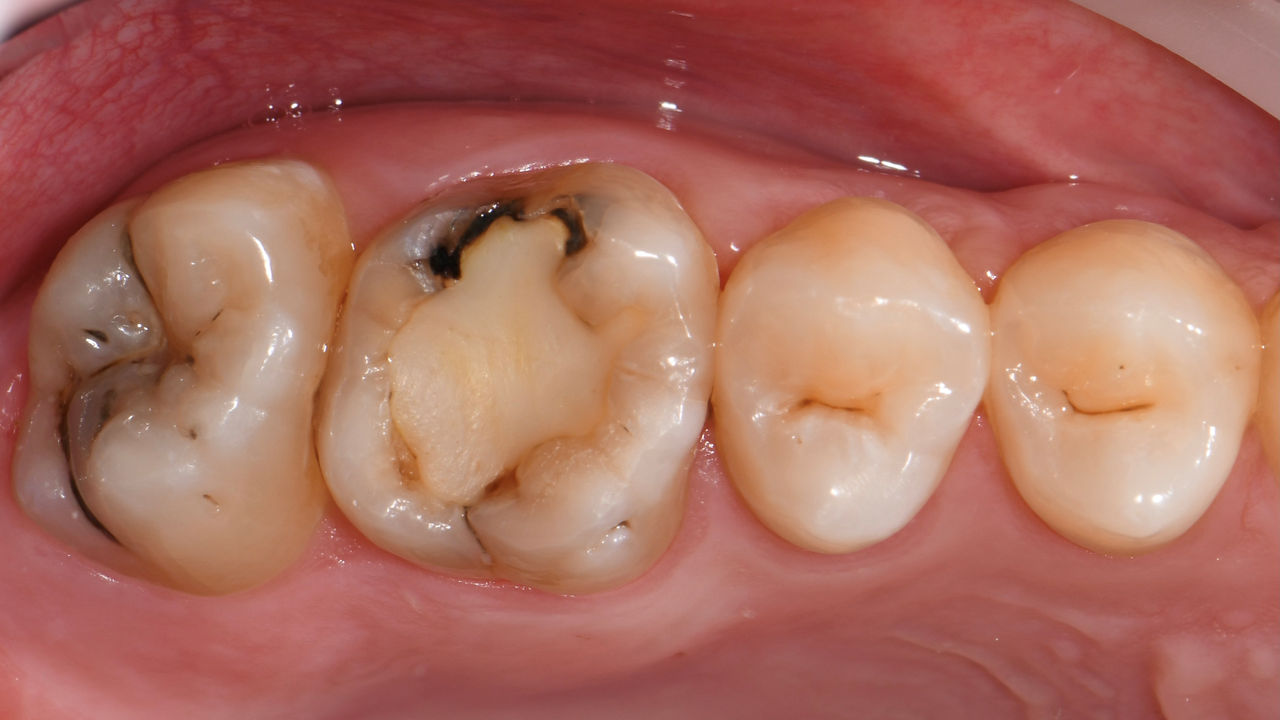

A lower second molar with sensitivity presented with cracks as well as an extensive Class I composite restoration on the buccal surface. According to the minimally invasive concept a CAD/CAM partial crown was planned, fabricated and bonded using CEREC Tessera in a single visit.

Before: Failed amalgam restoration needing replacement. Patient complaining of sensitivity and tooth presenting multiple cracks.

After: Chairside CAD/CAM partial crown restoration fabricated with CEREC Tessera Advanced Lithium-Disilicate glass ceramic.

Lower second molar chairside restoration

A partial CEREC Tessera crown